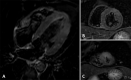

Concomitant acute myocarditis and acute coronary thrombosis is a rare presentation of acute chest pain in the emergency department, although the association between acute infections with a variety of pathogens and an increased risk of myocardial infarction has been reported. A case of acute myocardial infarction associated with acute myocarditis caused by coronavirus 229E in a middle-aged man without risk factors for coronary artery disease is described here. Coronary CT angiography with late enhancement protocol revealed areas of myocarditis and infarction, and cardiac MRI and coronary angiography were then performed. © RSNA, 2021.